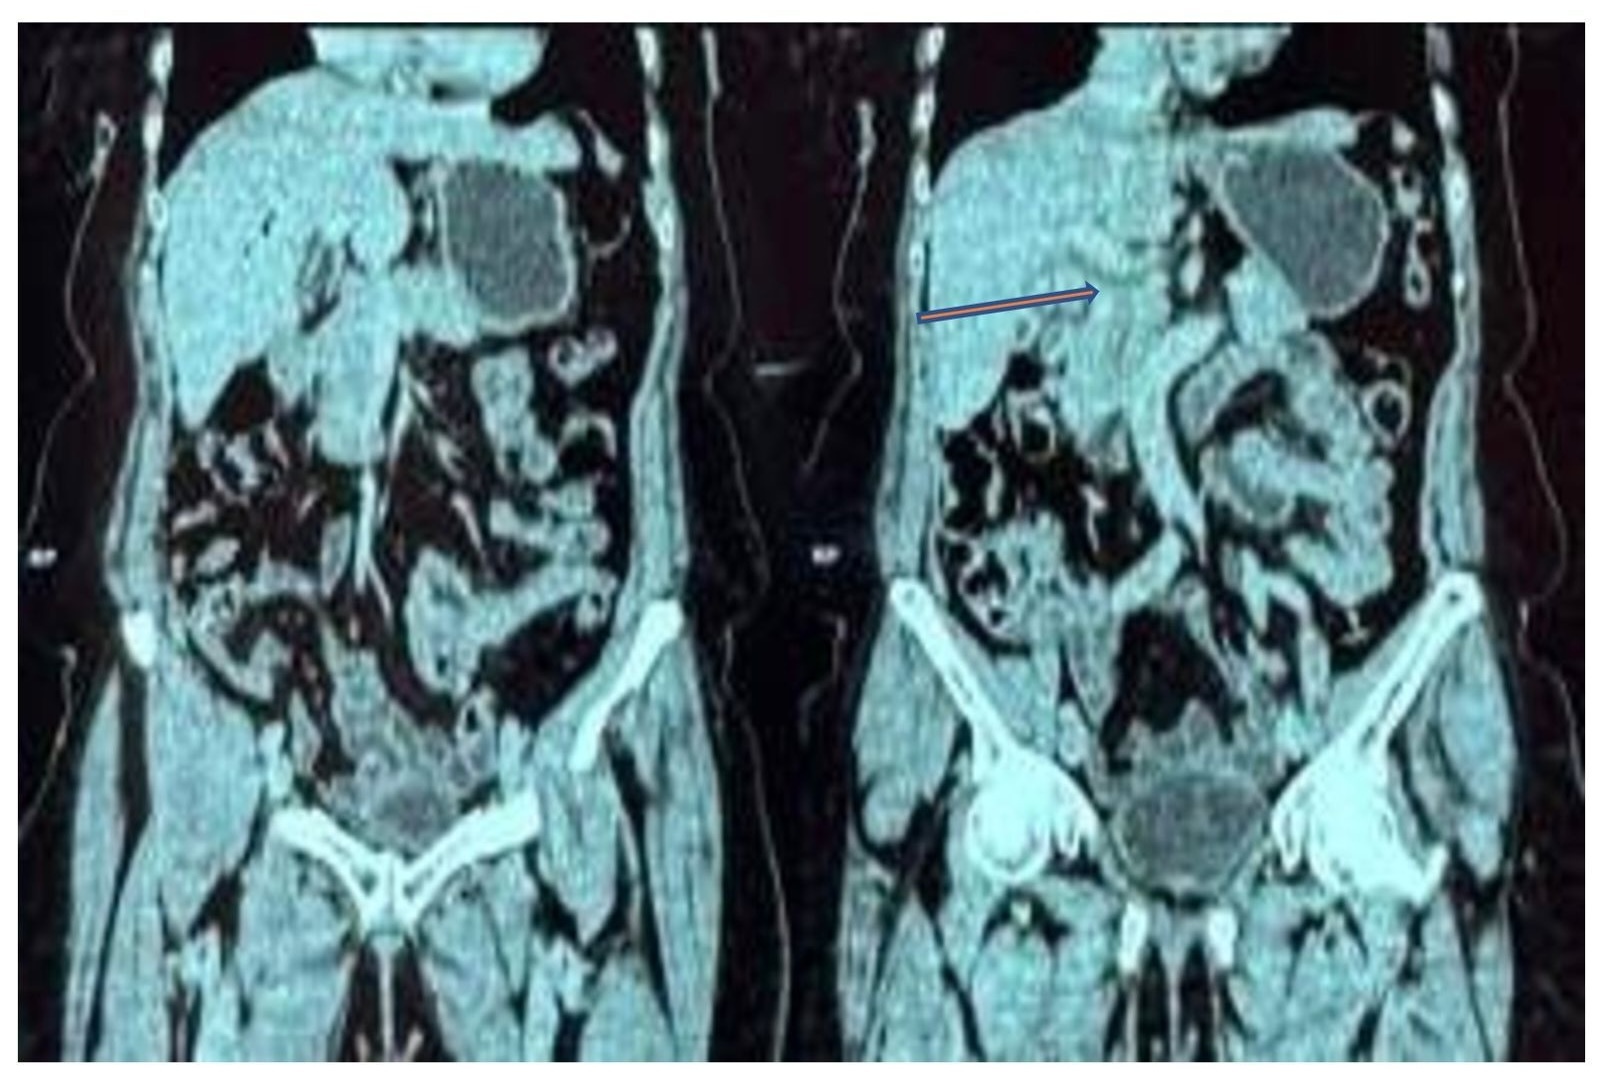

Following the persistence of these symptoms, she sought medical attention at a primary facility where some tests were done which showed leucocytosis of 14000/ul (4-10000/ul). A liver function test showed a cholestatic picture with ALP at 259 U/L (53-153U/L), GGT at 112U/L (11-52U/L), and direct bilirubin at 28U/L (0-5U/L). A Computed Tomography (CT) scan (Figure 1) done showed a thickened gallbladder wall measuring 3.5 mm with biliary sludge. There was mild intrahepatic and extrahepatic biliary duct dilation with pneumobilia. The CBD measured 16.5mm and a tapering was noted in its distal portion. No stones were noted. These features were in keeping with acute-on-chronic cholecystitis. With a differential of acute cholangitis. A Magnetic Resonance Cholangiopancreatography (MRCP) (Figure 2) showed perihepatic collection, dilated CBD, and two lamellated calculi, measuring 9mm and 13mm, were identified in the proximal CBD, along with a distended, calculous gallbladder. A diagnosis of cholelithiasis with cholecystitis and obstructive choledocholithiasis was made. Subsequently, she was given intravenous antibiotics and Endoscopic Retrograde Cholangiopancreatography (ERCP) was done with CBD stone extraction and stenting. Three weeks later, her symptoms subsided and she was then referred to our facility for laparoscopic cholecystectomy.